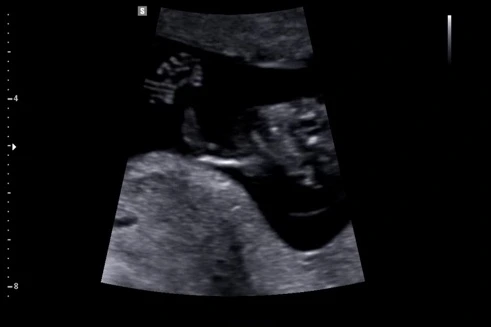

손뼉 치는 아기

그동안 질초음파만 보다가 처음 복부초음파를 봤는데 신세계였다. 아직 얼마 나오지 않은 내 배에서 오랜만에 본 6cm가량 되는 내 아기는 이제 올챙이나 공룡이나 곰돌이 인형의 모습이 아닌 사람의 모습을 하고 있었다. 손가락과 발가락도 모두 확인할 수 있었다.

아기가 박수도 치네요!

아직 태동을 느끼진 못하지만 복부초음파에서 본 아기는 발을 뻗고 손을 입으로 끌어당기며 열심히 움직이고 있었다. 의사 선생님이 아기가 박수도 치네요! 하면서 영상을 만들어주셨다. 손을 끌어모으는 영상이지만 어찌 보면 손뼉 치는 것으로 보이기도 한다. 신기하고 감격스러웠다.

아기가 조금 더 자라면 곧 태동을 느낄 수 있겠지? 내 뱃속에서 아기가 움직이는 걸 느낄 때마다 깊고 잔잔한 감동을 느낄 것 같다. 움직임이 커서 의사 선생님이 검사하는 데 시간이 오래 걸렸다. 그마저도 귀여웠다.